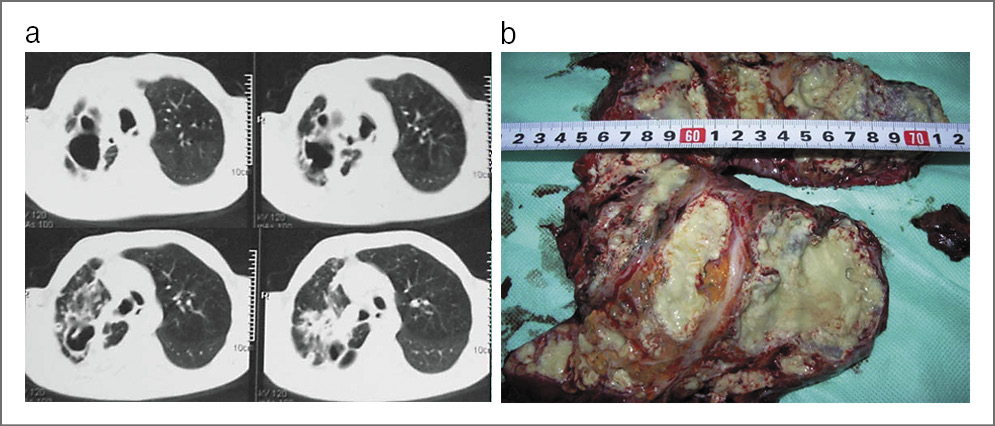

– Я понимаю, о чем Вы говорите. Но я могу доказать свою точку зрения. Приведу небольшую статистику лечения лекарственно-устойчивого туберкулеза легких на нашей базе НИИФП ФГАОУ ВО «Первый МГМУ им. И.М. Сеченова» (Сеченовский Университет) с 2011 по 2017 г. В основном это пациенты с разным типом лекарственной устойчивости (табл. 1). Почти у 70% всех больных – ФКТ (рис. 3), у 25% – туберкулема (рис. 4). Особую опасность представляет казеозная пневмония, так как без оперативного вмешательства смертность может достигать 99% (рис. 5).

Рис. 5. Казеозная пневмония: а – на КТ органов грудной клетки; b – на макропрепарате.